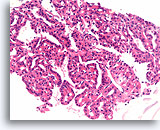

Afbeelding 15

Benigne, hyperplastisch/adenomatoïde nodule, schildklier FNA, celblok.

Dicht fibreus weefsel (niet actief desmoplastisch) met hemosiderine en beduidend atrofische, afgeplatte follikels kunnen worden waargenomen.

40X

Afbeelding 15

Benigne, hyperplastisch/adenomatoïde nodule, schildklier FNA, celblok.

Dicht fibreus weefsel (niet actief desmoplastisch) met hemosiderine en beduidend atrofische, afgeplatte follikels kunnen worden waargenomen.

40X